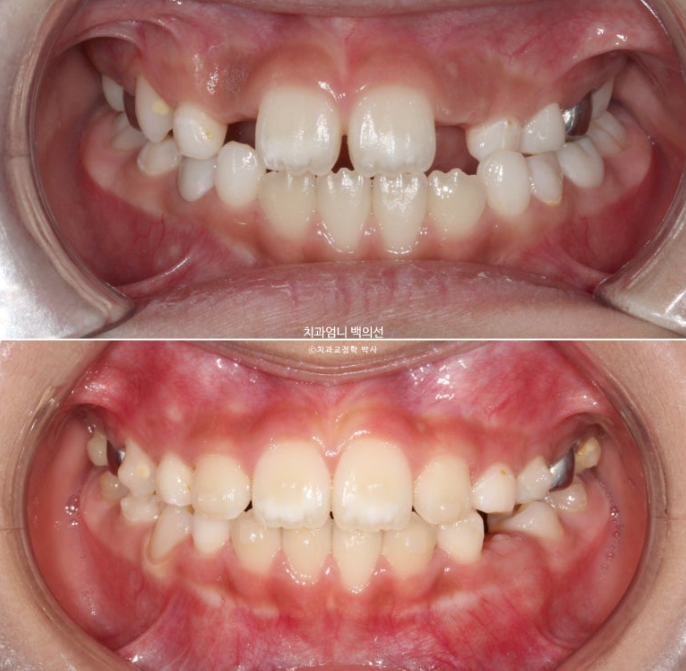

24년 12월부터 25년 6월까지 두번째 세트 19개 장치를 모두 낀 후 모습입니다.

측절치를 포함한 앞니는 잘 배열 되었습니다.

윗니가 아랫니를 잘 덮도록 앞니 교합이 개선되었습니다.

유치송곳니 벌어진 부분은 영구치 송곳니가 나올 때 공간이 부족하지 않도록 의도적으로 형성한 공간입니다.

영구치 맹출 공간은 충분하고 배열과 중심선 교합 모든 게 좋습니다.

1년 6개월간의 변화를 보겠습니다.

장치를 낀 기간은 9개월이고 영구치 맹출을 기다리며 쉰 기간은 7개월 입니다.

23.12~25.06

앞니 중심선은 정확히 맞고 배열은 좋습니다.

윗니가 아랫니를 정상적으로 덮지 못하는 절단교합 이었으나, 3급 고무줄로 적절한 앞니교합을 형성했습니다.